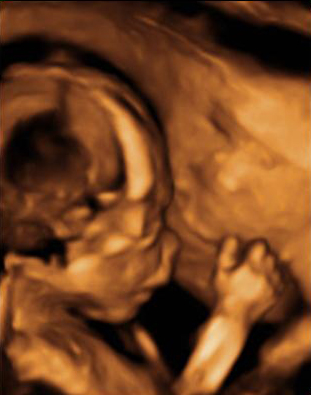

Ecografía Embarazo 4D Semana 20 - MALFORMACIONES FETALES